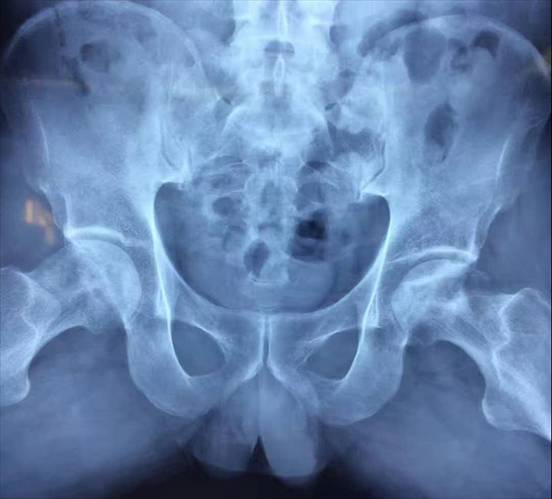

骨盆骨折合并内脏损伤诊疗、老年髋部骨折手术治疗、复杂开放性骨折合并血管神经损伤术、慢性骨髓炎根治手术、开放性骨折术、神经血管损伤术、骨与软组织缺损手术、断肢断指再植术及多种复合皮瓣修复肢体复杂创面等。

沈金虎 创伤专科主任 主任医师 教授 医学硕士

全国中西医结合创伤专业委员会委员,徐州市足踝外科专业委员会委员,徐州医学会医疗事故技术鉴定和医疗损害鉴定专家库成员。擅长治疗复杂严重的多发伤复合伤,利用MIPPO技术治疗复杂的四肢长骨干及关节周围骨折、骨盆及髋臼骨折;慢性骨髓炎、骨肿瘤和骨缺损的修复重建;熟练利用腓肠神经营养皮瓣修复足踝部皮肤缺损;熟练掌握骨质疏松症的诊断及治疗,利用微创技术治疗老年髋部骨折、胸腰椎骨质疏松性病理骨折。主持市级课题1项,参与国家自然基金课题1项,省级课题2项。专家门诊时间:每周一、四全天。